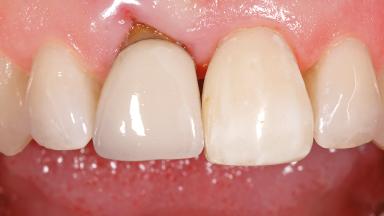

Early Placement of an Implant in a Maxillary Right Central Incisor Site

This 41-year-old female patient was referred to the clinic for the replacement of the right central incisor, since the tooth had developed a root fracture in the long axis that made extraction necessary. The healthy, non-smoking patient was first seen with the tooth still in place. A detailed Esthetic Risk Assessment was performed.The patient was worried about her dental esthetics and had high expectations for a successful treatment outcome from an esthetic point of view. The patient had a medium lip line that displayed parts of the gingiva in the anterior maxilla upon smile.

Defining Characteristics One missing tooth to be replaced by an implant-borne crown

Mesio-Distal Space Symmetry +/- 1 mm of contra-lateral tooth